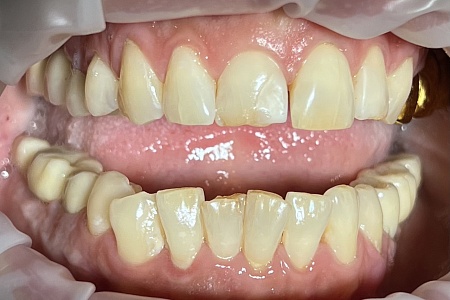

Работы наших врачей